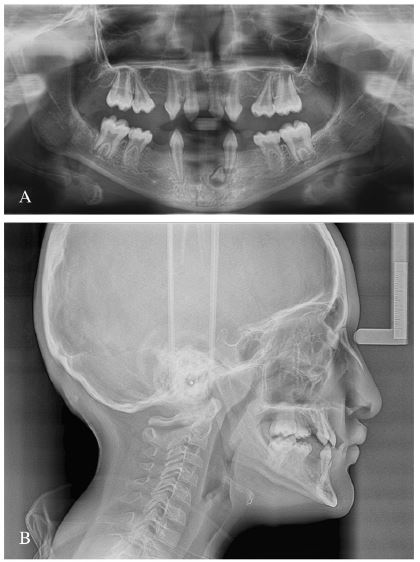

Panoramic X-ray confirmed oligodontia of deciduous and permanent teeth. Permanent first molars close to the dental eruption with alteration of the shape of the pulp chamber, typifying taurodontism. Additionally, a dental germ was observed apical to tooth 7.3 (figure 2 (A)). The lateral skull radiography (figure 2 (B)) allowed a cephalometric analysis, including the cephalometric measurements used by the American Association of Orthodontics. A class III skeletal relationship was observed, due to maxillary deficiency (ANB = -5º, angle of convexity = -14º; SNA = 74º), with a slightly counter clockwise growth tendency (Y-axis = 59º; Sn.GOGn = 28º; FMA = 23º). The inter-incisor relationship could not be assessed due to the absence of the lower anterior teeth (table 1).